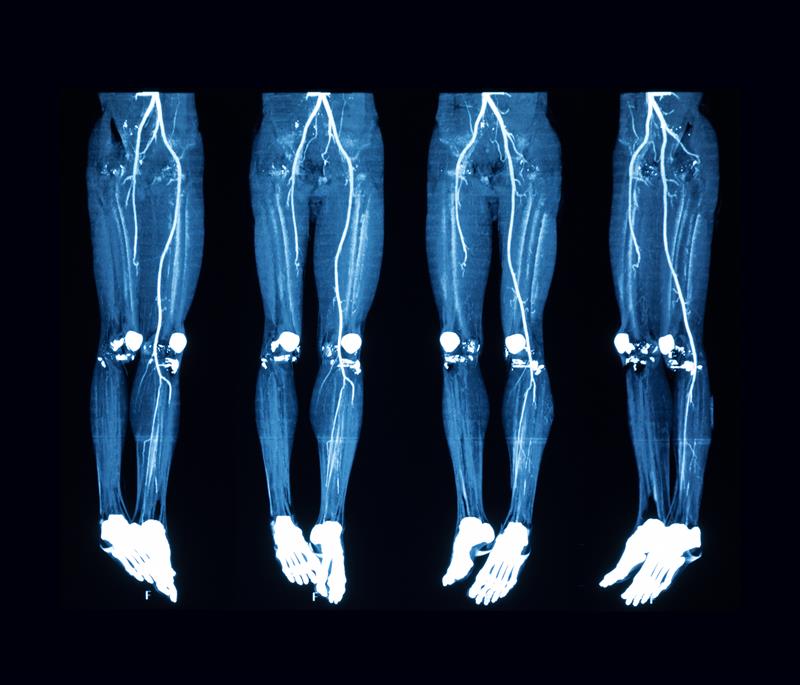

Angiography

Angiography is an advanced diagnostic imaging procedure that visualizes the blood vessels of the heart to identify blockages or narrowing that could restrict blood flow. At Narayan Swaroop Hospital Kaushambi Prayagraj, this test is performed by skilled interventional cardiologists using state-of-the-art cath lab technology, enabling accurate detection and timely treatment of heart diseases.